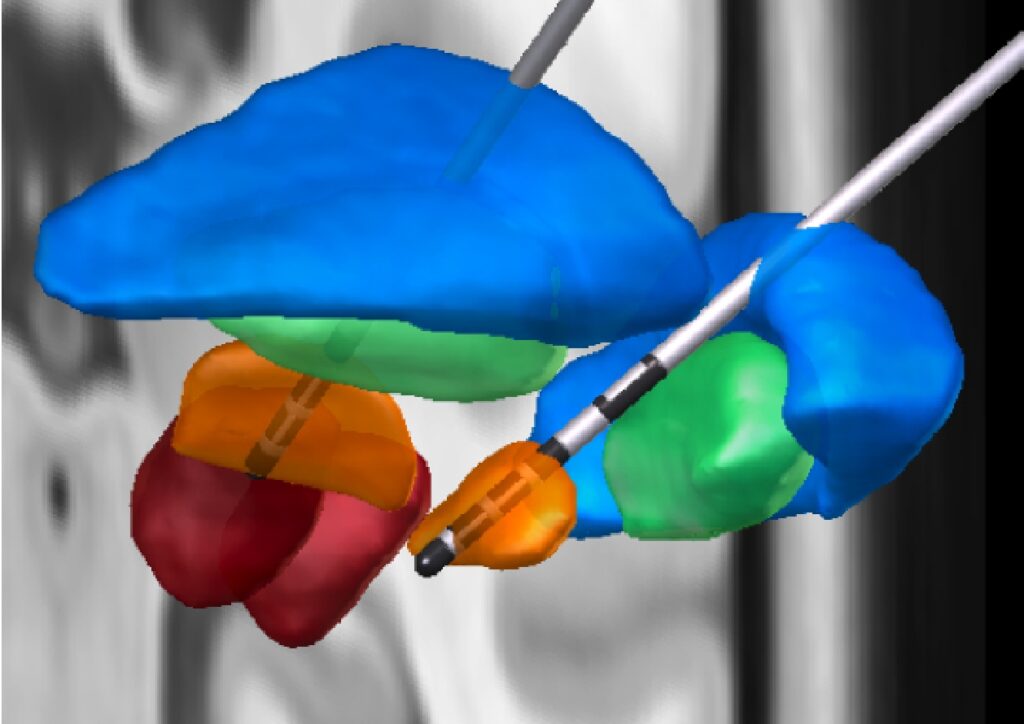

本講座では、てんかん治療の一環として、頭蓋内電極を用いた皮質脳波計測(Electrocorticography、Stereotactic EEG)を行っています。この手法は、てんかん発作の焦点を特定し、最適な治療法を見つけるために不可欠なものです。また、パーキンソン病や本態性振戦を対象とした脳深部刺激療法(Deep Brain Stimulation)の電気刺激装置の埋め込み時に神経活動計測を行っています。これらの計測時、患者様にご協力いただき、認知活動時・安静時のヒトの皮質脳波計測も行っております。すべての計測は、安全かつ配慮された環境で行われ、患者様の状態に十分注意を払いながら実施しています。国内外の研究機関との共同研究により、最先端の解析技術を用いて脳の働きについての新たな知見を得ることで、ヒトの認知機能の神経学的解明や将来の治療法の開拓を目指しています。

本講座では、次の脳刺激手法を活用した多数の臨床研究を実施しています。脳深部刺激療法(Deep Brain Stimulation, DBS)、経皮的磁気刺激(Transcranial Magnetic Stimulation, TMS)、および経皮的耳介迷走神経刺激(Transcutaneous Auricular Vagus Nerve Stimulation, taVNS)を用い、脳刺激の作用機序の解明や脳刺激が認知機能に与える影響の調査に取り組んでいます。